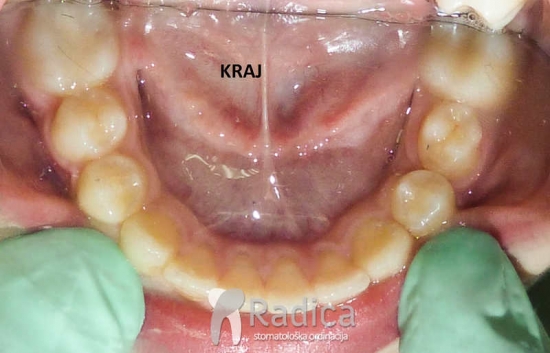

1. Prerani gubitak mliječnih molara. Lingvalnim lukom spriječavamo pomak trajnih molara naprijed.